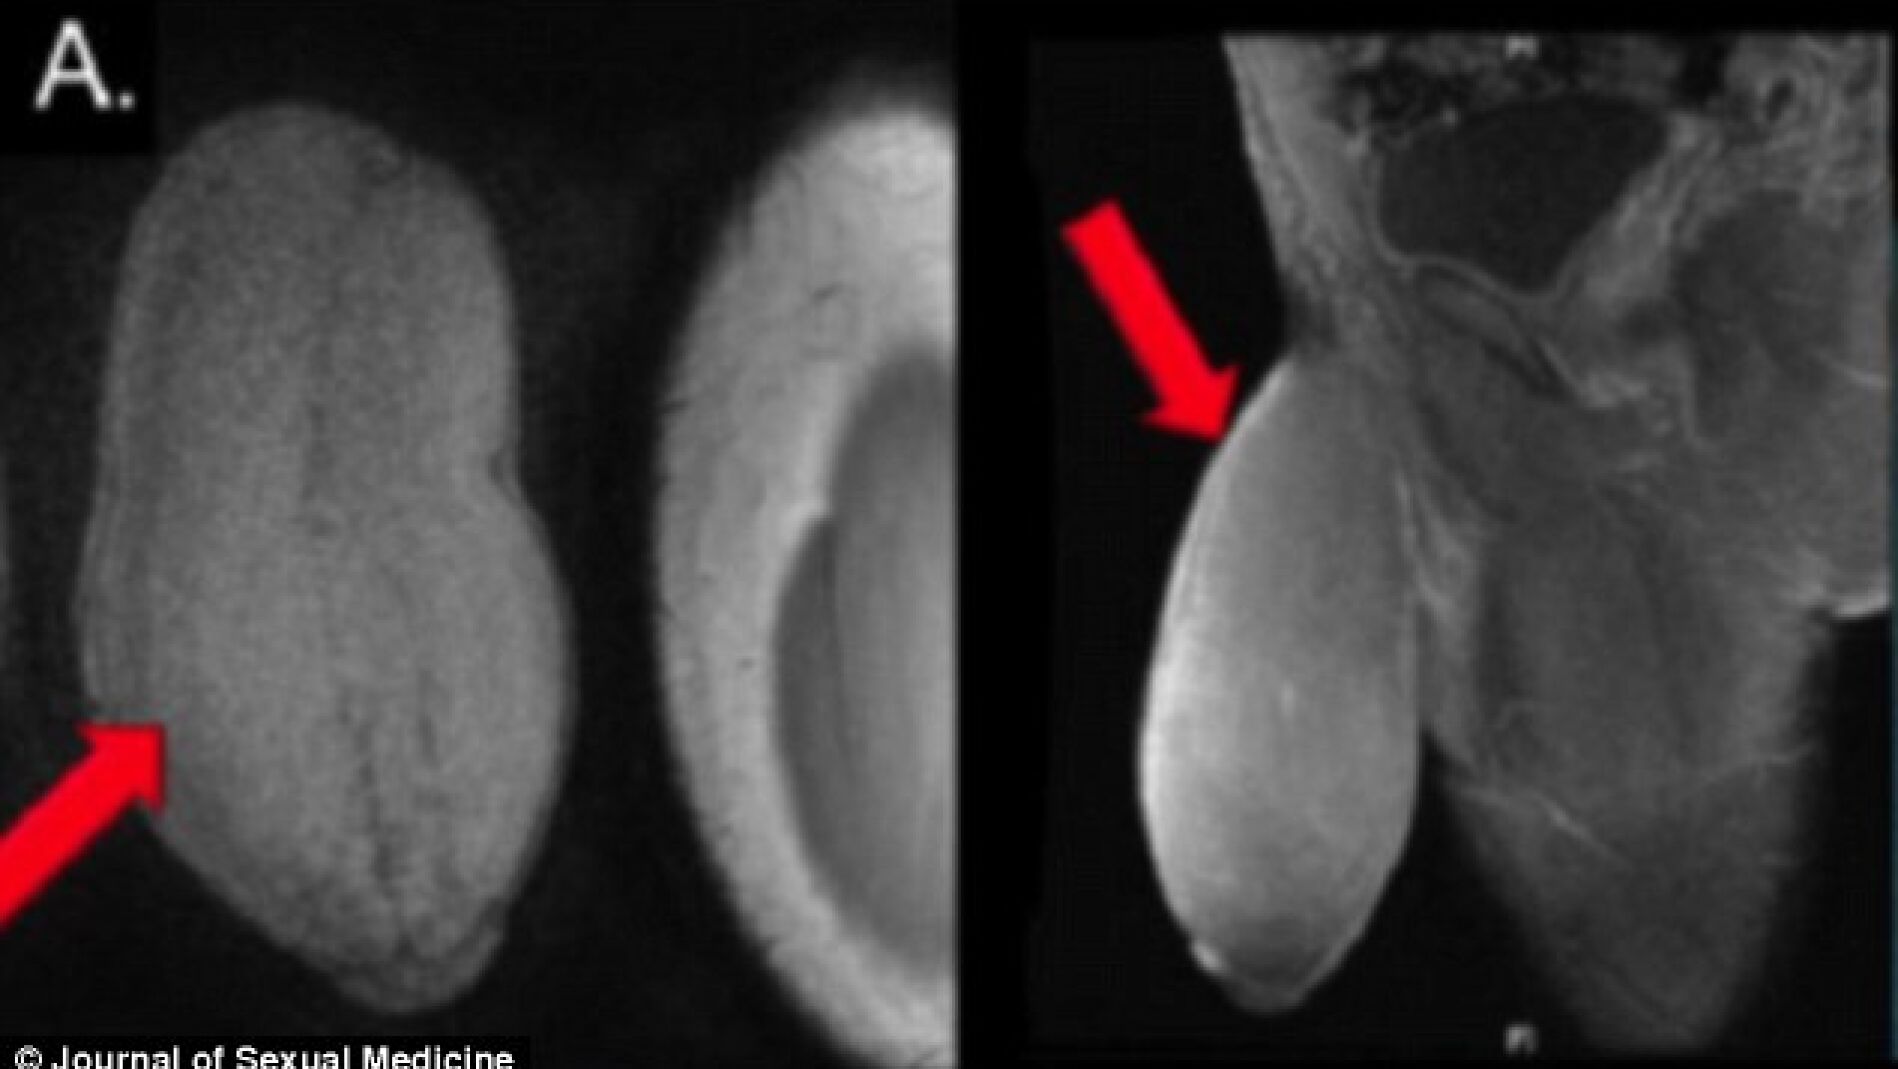

El adolescente pasó dos días en el hospital antes de regresar a casa. Declaró sentirse "muy contento" con su nuevo pene. Los médicos no tomaron medidas finales del pene, aunque el Dr. Carrión aseguró que el resultado fue "generoso".

"Es un poco más largo y ligeramente más grueso que el promedio, pero ahora parece simétrico, y el paciente se mostró muy satisfecho", dijo. "El adolescente tiene ahora erecciones normales y su miembro es visualmente atractivo.", amplió el cirujano. Desde que la historia se ha hecho pública un nuevo paciente ha solicitado someterse a la intervención. "Tiene un pene de grandes dimensiones de forma natural, no ha padecido ninguna anomalía", declaró el doctor Carrión.